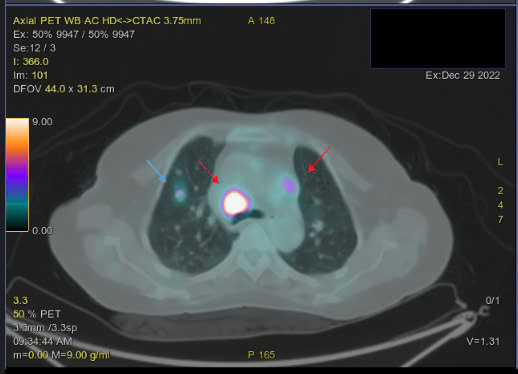

Hình ảnh PET/CT với F18-FDG đánh giá giai đoạn trước điều trị:

Hình 1. Hình ảnh tăng chuyển hóa FDG ở nhiều vị trí hạch trên và dưới cơ hoành và các cơ quan khác ngoài hạch

Hình 2. Hình ảnh nốt tổn thương ở phổi và hạch trung thất

Hình 3. Hình ảnh hạch bẹn kích thước lớn tăng chuyển hóa FDG

– Hình ảnh hạch cổ 2 bên, hạch trung thất, hạch ổ bụng, hạch bẹn 2 bên tăng chuyển hóa FDG hướng tới ác tính.

– Hình ảnh nốt tổn thương phổi phải, tổn thương xương bướm, tăng chuyển hóa FDG hướng tới ác tính.